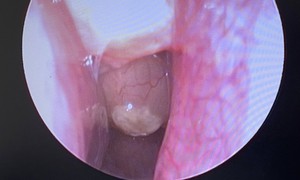

Cứu người bị áp xe ổ bụng hiếm gặp do mắc xương cá

Tin nóng y tế - 09/10/2025 20:05SKĐS - Chiều 9/10, Bệnh viện Lê Văn Việt (TPHCM) cho hay, các bác sĩ khoa Ngoại Tổng hợp vừa phẫu thuật thành công một ca áp xe ổ bụng do dị vật xương cá có thể nguy hiểm đến tính mạng nếu chậm trễ xử trí.